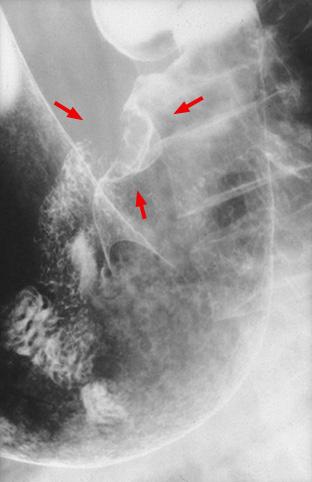

疾患(病理主体)の分類悪性上皮性腫瘍/腺癌

部位(臓器別)胃(部位)/前庭

検査方法X-P

腫瘍の肉眼分類1型(腫瘤型)/

病変の最大径(ミリ)25〜29

腫瘍の深達度s(a)